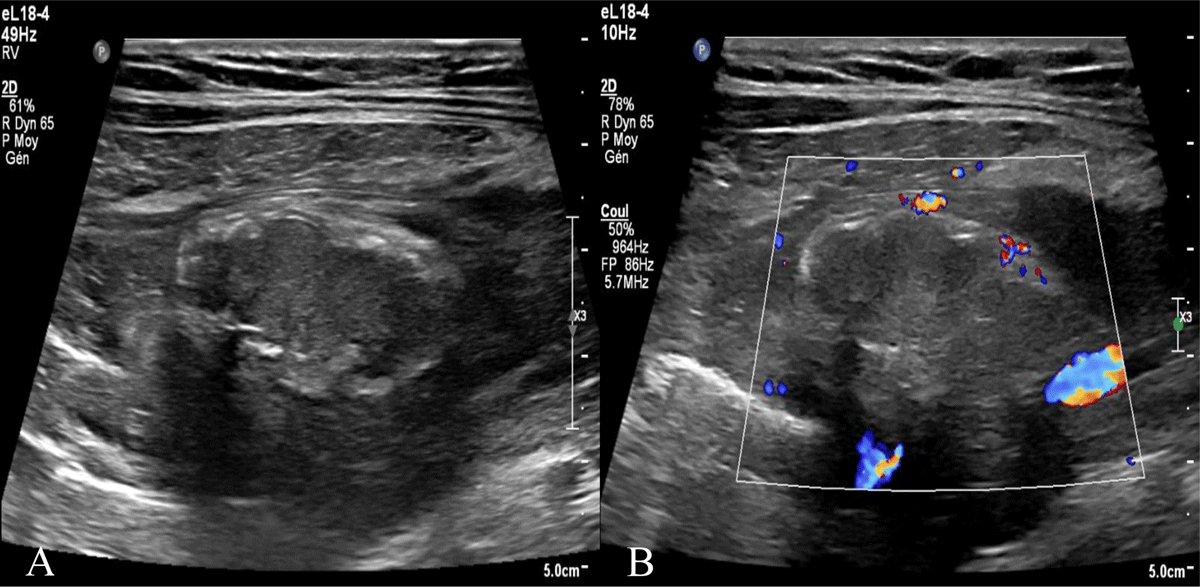

Figure 1

Right iliac fossa ultrasound. A) Superficial intraperitoneal oblong mass in the right iliac fossa of 35mm non-compressible, hyperechoic, surrounded by a subtle hypoechoic line. B) without internal vascularity.